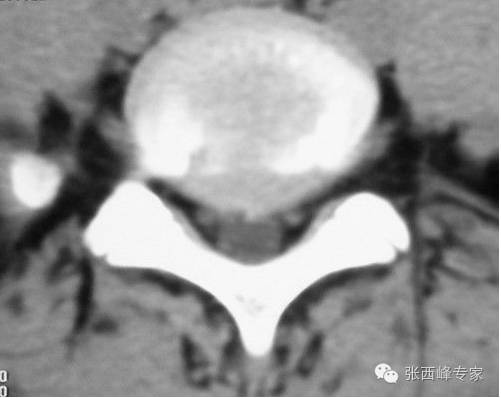

CT腰5骶1椎间盘突出